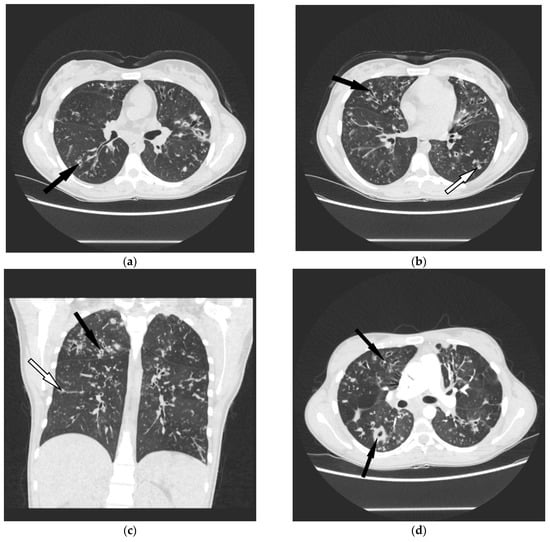

4.3. Radiological Data